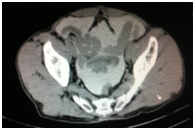

Diagnostic and treatment processes of patients was carried out according to the diagnostic algorithm developed in the Republican research center for emergency medicine at injury of a bladder taking into account the dominating pathology. On this diagnostic algorithm taken patent from Agency on intellectual property of the Republic of Uzbekistan. No. DGU 2010 0177. The valuable diagnostic method of bladder injury is retrograde cystography. At doubtful cases CT more precisely allows to determine the volume and nature of bladder injury and to estimate condition of other associated lesions. At 5 (4.2%) patients the isolated injury of a bladder managed by laparoscopic repair of a bladder rupture on an urethral catheter (Figures 1 & 2).

Figure 1 Retrograde CT cystogram. Bladder filled with contrast. Extravasation of contrast.